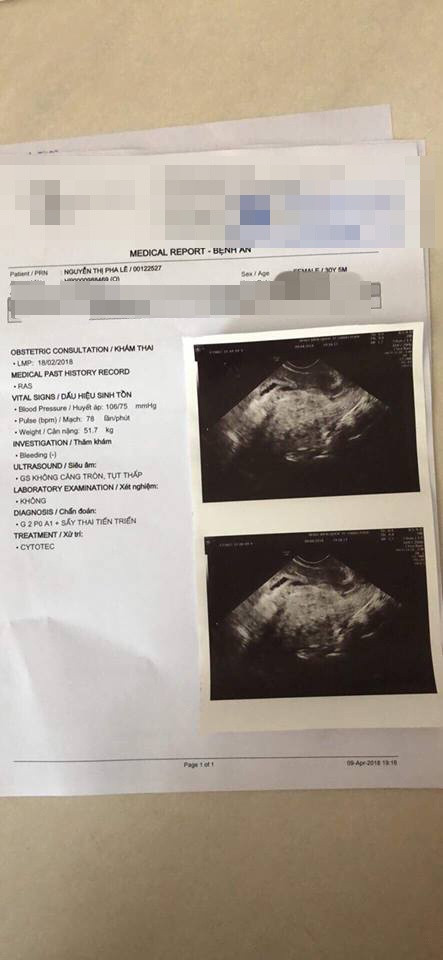

7 ngày nằm viện trong sự lo âu vì bác sĩ thờ ơ và không biết thai nhi trong bụng mình ra sao khiến Pha Lê vô cùng bức xúc, mệt mỏi. Chính vì vậy, cô đã quyết định xin ra viện để đến một bệnh viện khác siêu âm. Kết quả nữ ca sĩ đã bị sẩy thai, điều này khiến cô vô cùng đau đớn.

"7 ngày chúng tôi được nuôi như heo, sáng ra phát thuốc là xong! Tự ăn tự lo không biết cuộc đời mình sẽ đi về đâu! Tới ngày thứ 7 là tôi đòi siêu âm bằng được đó! Kết quả vẫn là phải ở lại viện điều trị! Tôi cảm thấy không ổn, tôi nói cô tôi làm thủ tục ra viện để qua bên... liền luôn! Họ yêu cầu phải viết giấy cam kết có chuyện gì sẽ không chịu trách nhiệm, ok tôi viết và kí và tôi photocoppy toàn bộ hồ sơ bệnh án mà họ dấu không cho tôi xem kể cả kết quả siêu âm sáng hôm ấy! 9h đi siêu âm rồi làm giấy ra viện mà 3h chiều mới được cấp giấy đi! Ok! Không sao! Tôi sang bên... khám lại liền...và kết quả là ổ bụng tôi sạch tinh không còn gì, có nghĩa là tôi đã sẩy từ lâu rồi mà sáng nay...vẫn nói tôi là phải nằm lại thử máu các kiểu điều trị tiếp và mỗi ngày vẫn cho uống viên an thai đồng nghĩa việc giữ lại máu độc trong người tôi... Hiểu rồi ha! Cách nhau vài tiếng mà 2 bản siêu âm khác nhau hoàn toàn luôn.... bạn nghĩ sao?", Pha Lê bức xúc kể.

Cùng một ngày, Pha Lê nhận được hai tờ siêu âm khác hẳn nhau khi đi khám ở hai bệnh viện.

Việc chọn sai bệnh viện đã khiến Pha Lê không được chăm sóc tốt. Khi đến một bệnh viện khác để siêu âm, cô mới đau đớn biết tin mình sảy thai.